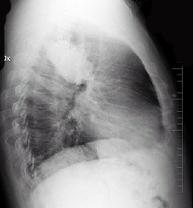

问题 男性,70岁,因胸痛就诊,不咳嗽、发热,X线检查如图,最可能的诊断是 ( )

选项 A、左肺炎性假瘤 B、支气管扩张 C、左侧叶间积液 D、左肺癌 E、左肺结核瘤

答案 D